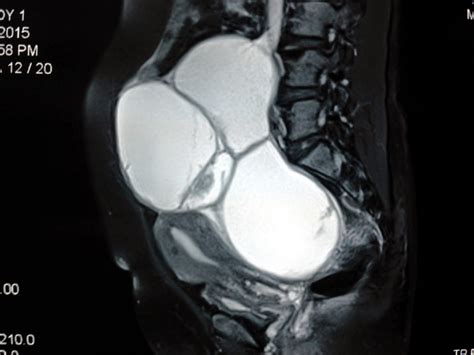

• Evaluating pelvic masses: If an ultrasound or physical exam detects a pelvic mass, doctors may order this test to help determine the likelihood that the mass is malignant or benign.

For these reasons, the blood work CA 125 is almost always used in conjunction with other diagnostic methods, such as:

• Imaging studies like CT scans or MRIs.